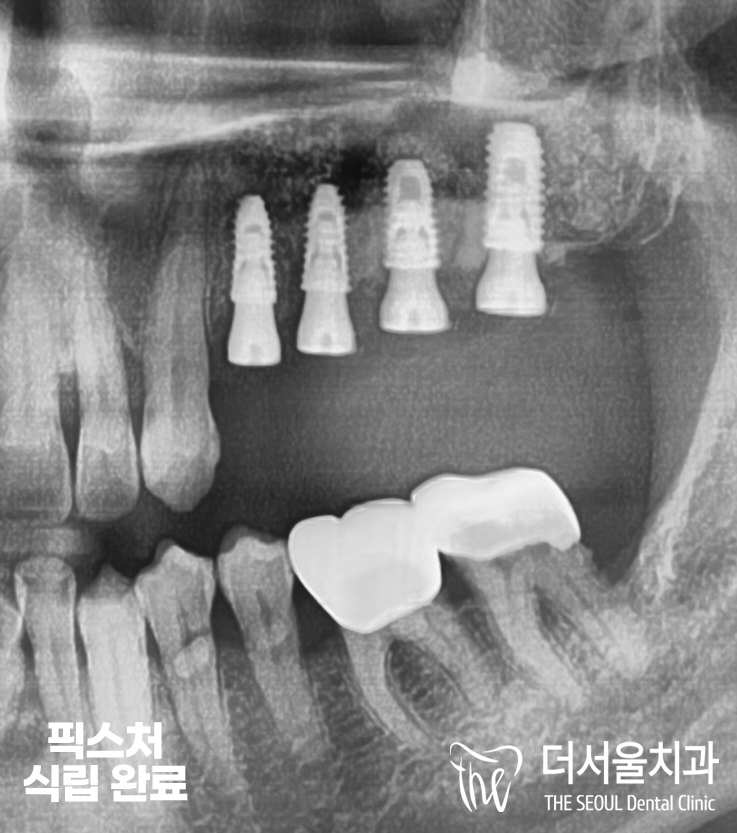

『고정체 식립 완료』

수진동치과 에서 24X27 위치에

픽스처 식립을 해드렸습니다.

혹시 그 주변에 뼈이식 재료가

심어져 있는 것을 볼 수 있으실까요?

하얀 뼈 재료들이 소복소복

채워져있는 것을 볼 수 있습니다.

이후 뼈와 고정체가 결합이

확실히 이뤄지는 것을 기다리며

크라운 제작에 들어갔습니다.